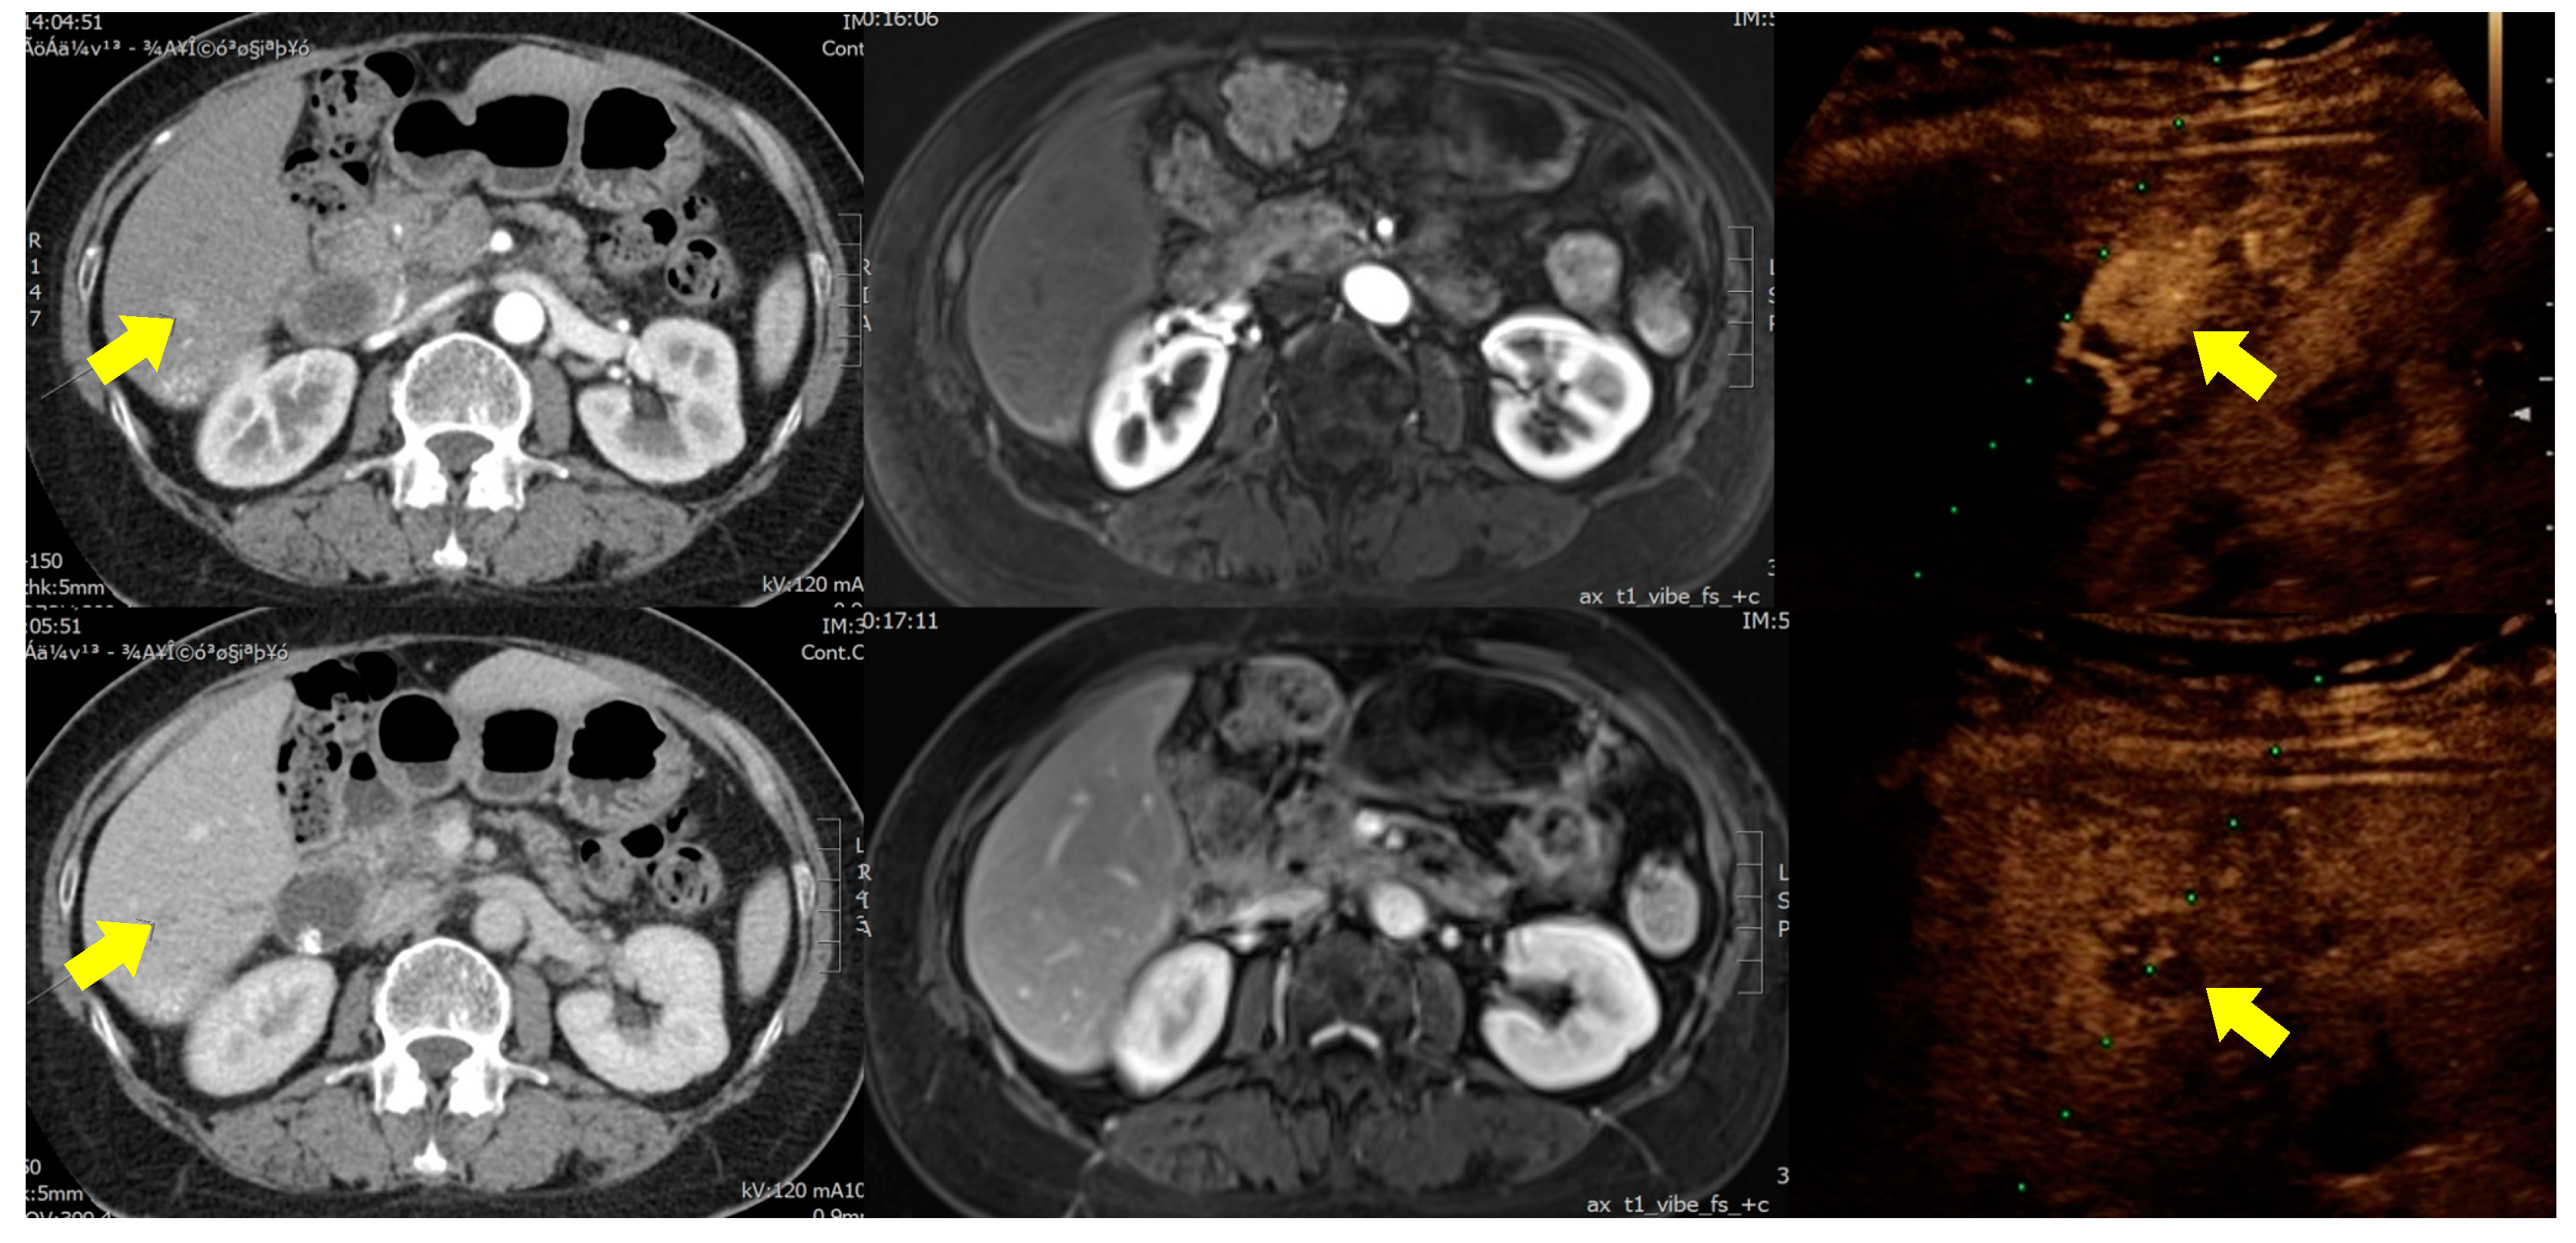

2.2. Examinations and Procedures

2.3. Data Interpretation